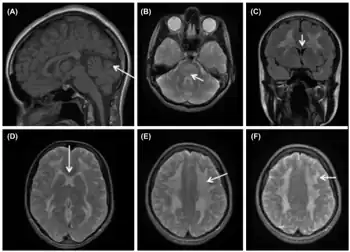

While the disease manifests early in life in most cases, diagnosis of the disease is often quite delayed.[1][3][4] The symptoms that affected patients present vary, but the most common presenting symptoms are gastrointestinal issues such as nausea, vomiting, abdominal pain, and diarrhea, and neurologic or ocular symptoms such as hearing loss, weakness, and peripheral neuropathy.[3] These gastrointestinal symptoms cause patients with MNGIE to be very thin and experience persistent weight loss and this often leads to MNGIE being misdiagnosed as an eating disorder.[1] These symptoms without presentation of disordered eating and warped body image warrant further investigation into the possibility of MNGIE as a diagnosis.[1] Presentation of these symptoms and lack of disordered eating are not enough for a diagnosis. Radiologic studies showing hypoperistalsis, large atonic stomach, dilated duodenum, diverticula, and white matter changes are required to confirm the diagnosis.[3] Elevated blood and urine nucleoside levels are also indicative of MNGIE syndrome.[1] Abnormal nerve conduction as well as analysis of mitochondria from liver, intestines, muscle, and nerve tissue can also be used to support the diagnosis.[1][3]